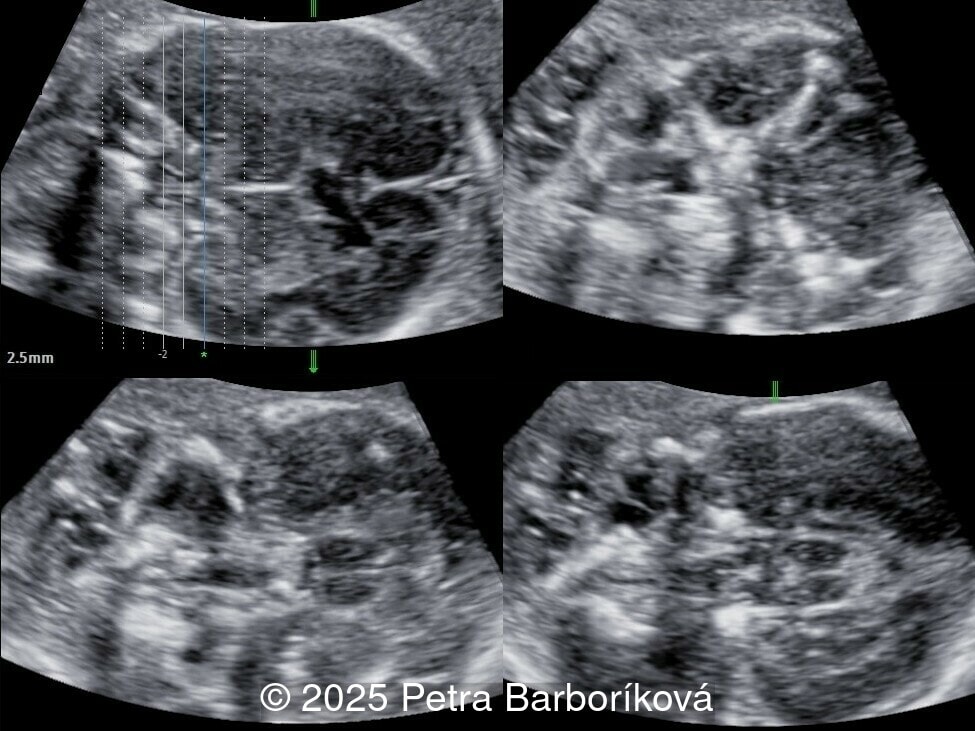

A 26-year-old primigravida with no significant past medical or family history was admitted at 18 weeks of gestation with preterm premature rupture of membranes. At 20 weeks of gestation, a detailed fetal ultrasound was performed under conditions of severe oligohydramnios, followed by fetal magnetic resonance imaging (MRI). Non-invasive prenatal testing (NIPT) for common aneuploidies was negative.

We present a case of agenesis of the cavum septum pellucidum (CSP).

At 20 weeks, detailed ultrasound under conditions of severe oligohydramnios demonstrated absence of the typical box-shaped anechoic structure of the cavum septum pellucidum (CSP). The frontal horns of the lateral ventricles appeared narrow and pointed, giving the characteristic “bull’s horns sign.” Multiplanar and 3D reconstructions confirmed the presence of the corpus callosum, while the CSP was absent. Other midline and posterior fossa structures appeared normal. The optic chiasm was partially visualized, although assessment was limited by technical conditions. Fetal magnetic resonance imaging (MRI) was subsequently performed and confirmed isolated agenesis of the CSP with preserved corpus callosum and posterior fossa structures. The optic chiasm and pituitary stalk are visible in the sellar region, but the pituitary gland itself is not clearly identified in the sella turcica as it is a very small structure. No additional central nervous system anomalies were detected.